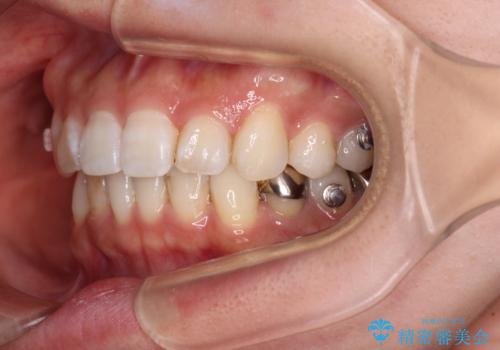

- 前歯のデコボコと深い咬み込みを気にして来院された患者様です。

インビザラインを用いて、前歯の叢生を解消するとともに、深い咬み合わせ(ディープバイト)を改善していくこととしました。

奥歯を後方に直立させることで深い咬み合わせを改善を図り、隠れていた下顎前歯が見えるほどになりました。